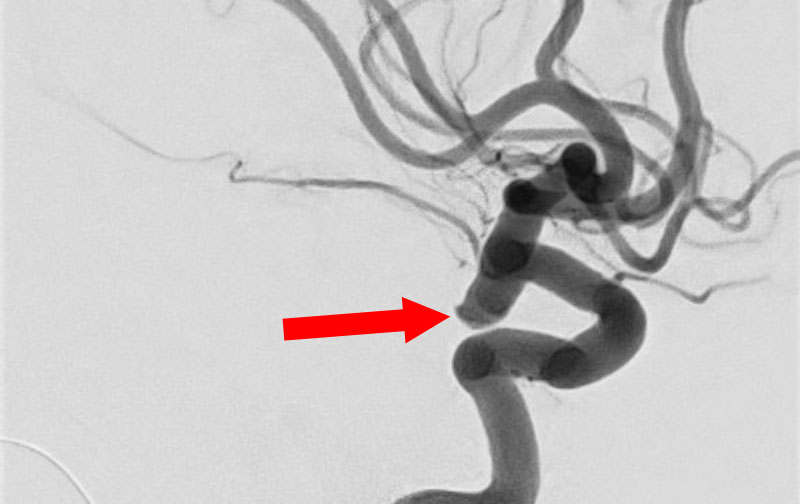

'25年11月

くも膜下出血

左中大脳動脈瘤破裂

40代

救急外来

No.1596 手術前

No.1596 手術中

No.1596 手術後